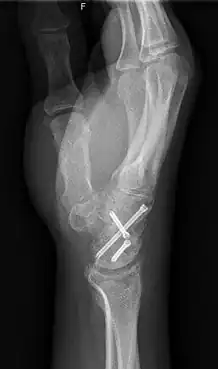

Arthrodesis

Arthrodesis is the surgical immobilization of bones within a joint to promote fusion of the joint.[5] Arthrodesis is performed most commonly on joints of the feet, hands, and spine.[6][7][8] Arthrodesis can relieve pain from arthritis and fractures.[9] This is accomplished through the use of orthobiologics such as allografts and autografts.[10] Allografts are done by creating bone grafts from a donor bone bank, whereas autografts are bone grafts from other bones in a patient's body.[10] Patient-reported outcomes following this procedure are typically positive in terms of long-term pain relief; however, the procedure also results in decreased range of motion.[11]